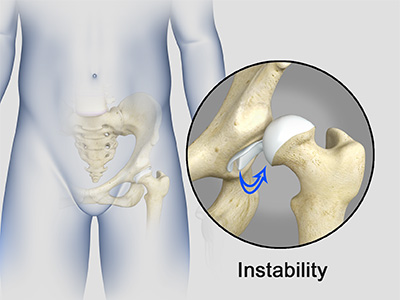

The hip joint is the junction where the hip joins the leg to the trunk of the body. It is comprised of two bones: the thigh bone or femur and the pelvis which is made up of three bones called ilium, ischium, and pubis. The ball of the hip joint is made by the femoral head while the socket is formed by the acetabulum. The Acetabulum is a deep, circular socket formed on the outer edge of the pelvis by the union of three bones: ilium, ischium, and pubis. The lower part of the ilium is attached by the pubis while the ischium is considerably behind the pubis. The stability of the hip is provided by the joint capsule or acetabulum and the muscles and ligaments which surround and support the hip joint.

The head of the femur rotates and glides within the acetabulum. A fibrocartilagenous lining called the labrum is attached to the acetabulum and further increases the depth of the socket.

- Acetabular labrum: The labrum is a fibrous cartilage ring which lines the acetabular socket. It deepens the cavity, increasing the stability and strength of the hip joint.

Femur Fracture Hip Instability

Hip Instability Hip Ligament Injuries